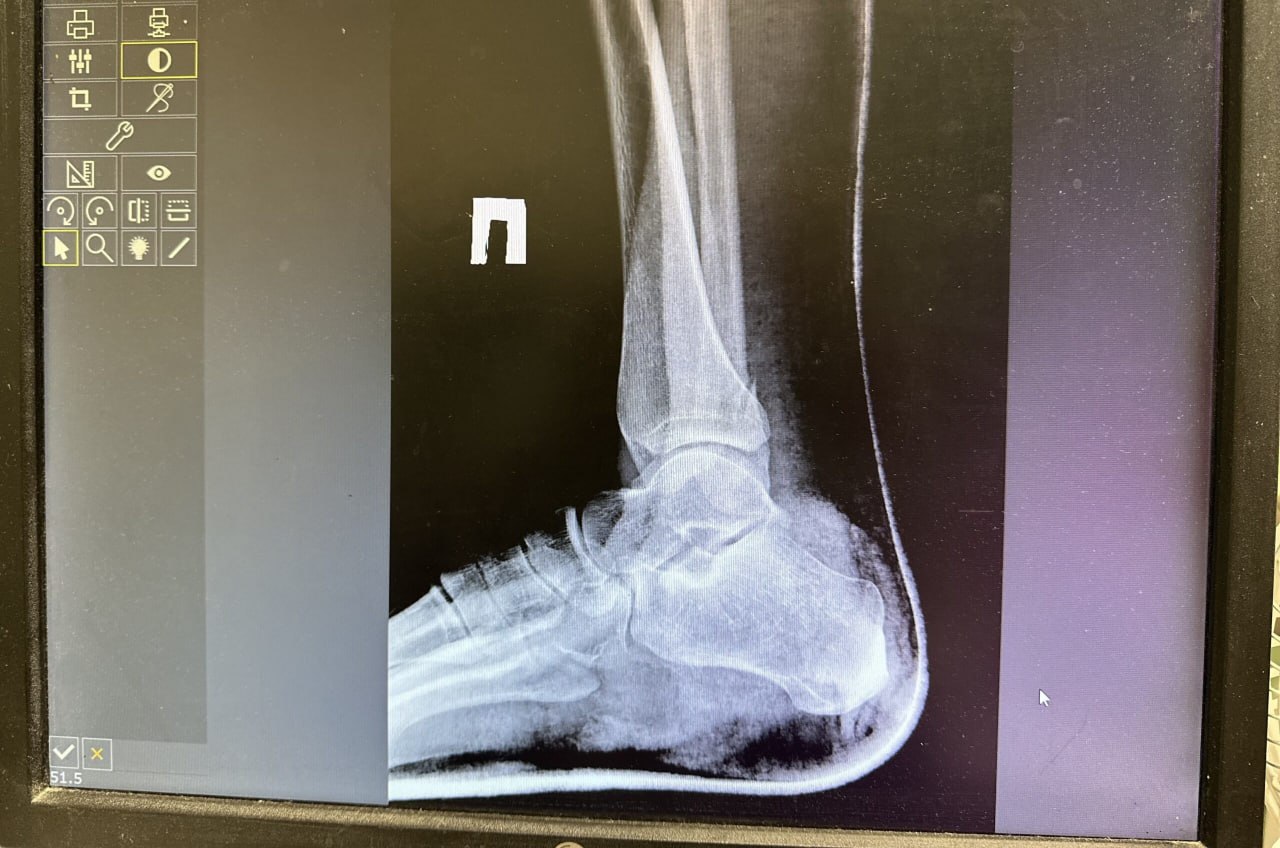

В ссоре она избила новую сожительницу бывшего супруга так сильно, что пострадавшая получила множественные переломы обеих ног.